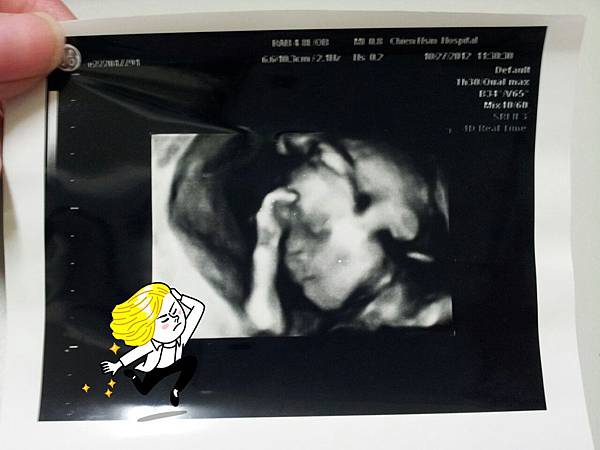

2012。10。27

越接近產檢日子月是緊張,當然沒有擔心嘿嘿的健康,因為一定是健康的呀!!!!!

是擔心要揭曉的XY問題

結果眼尖的阿爹一眼就看到了重點 XY

明明我們兩個期待的都是來個漂亮妹妹,而且他比我還排斥男生,結果他還在外人面前訓斥我要接受

當天的超音波,明顯的一根鳥鳥聳立在我們的面前

嘿嘿:阿爹、阿娘、阿姐~你們就接受吧!!!!